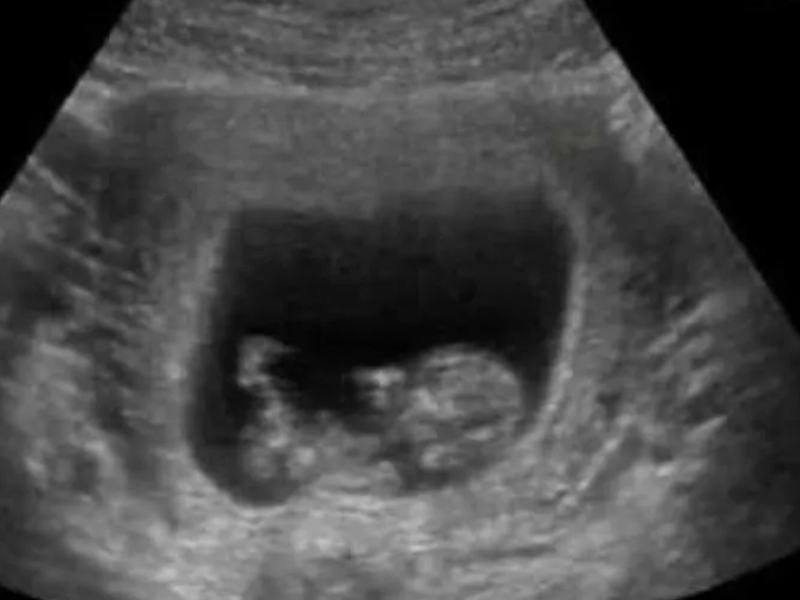

En el momento que la obstetra pasó el escáner a la altura del rostro del feto, este volteó, abrió los ojos y esbozó lo que parecía una sonrisa, sin embargo, lejos de que el resultado fuera una tierna postal, los sensores registraron lo que parecía el retrato de un "bebé demonio", como la misma Alston lo catalogó.

Resulta que la madre adolescente, que en aquel momento estaba en la semana 24 de gestación, va a parir a una nena y a pesar de que la imagen la impactó, ella no deja de sentir amor y ternura por su pequeña.